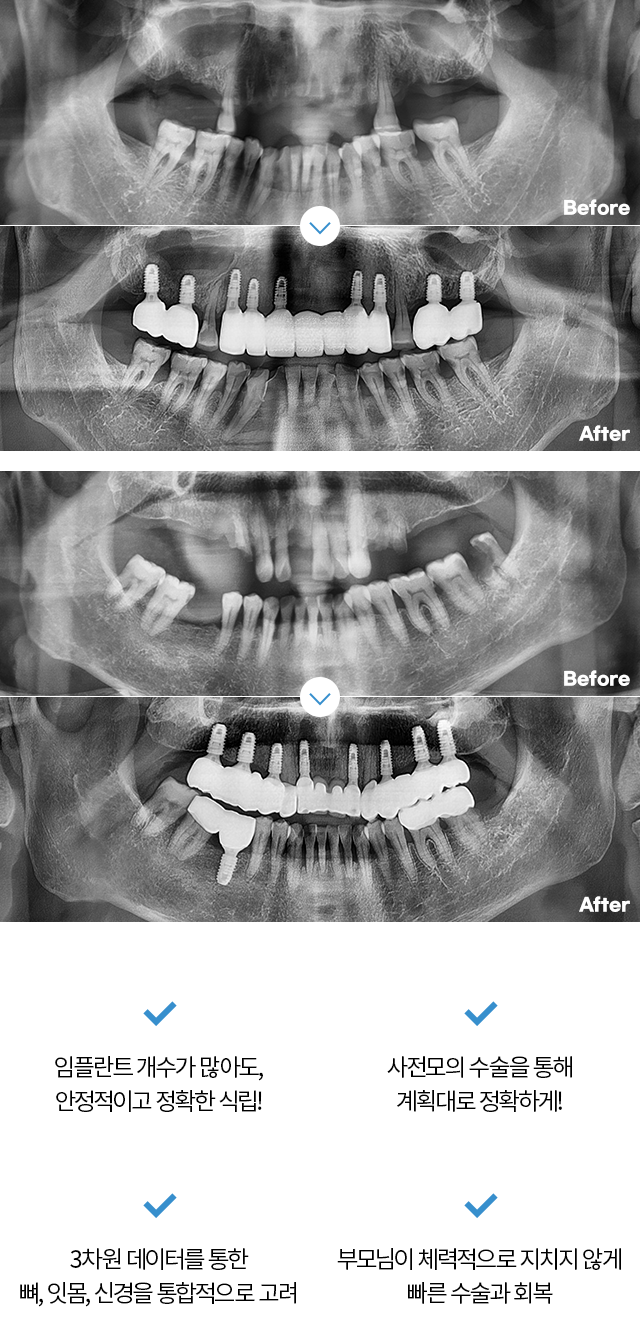

Before & After

치료 후 1년이 지난 모습입니다.

- 전체보기

- 임플란트